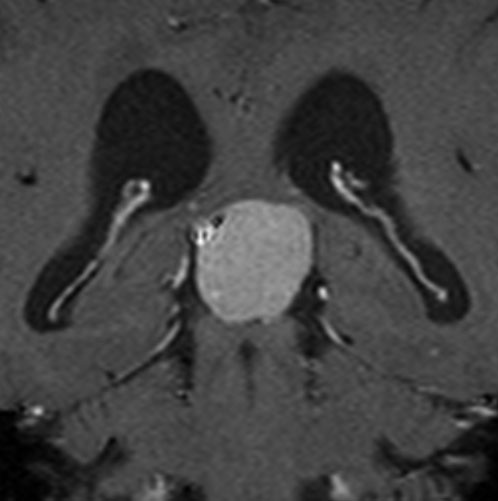

鞍結節部から視神経管を伝わり視神経鞘に伸びていた例です。鞍結節部と視神経管での視神経圧迫があったのでそこを除圧するために摘出したのですが,グレード2の髄膜腫で再発しました。下のMRIは,放射線治療 50Gy/25frしてから5年後の画像です。腫瘍は大きくなっていませんし,右の視力はVd 0.5あり,有用視力といえるほどの視野ではありませんが,視野は上の方で残っています。